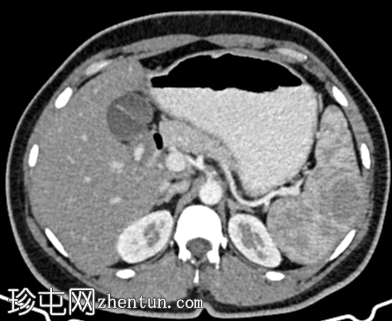

轴位增强扫描

动脉期

脾脏内可见一圆形低密度病灶,动脉期呈周边环状强化,延迟期呈轻微向心性充盈

未见钙化、动静脉畸形或动脉瘤

学特征为:病灶周围呈放射状强化,中心呈放射状强化,周围环状强化,中心充盈轻微。增强扫描后可见中央星状瘢痕。